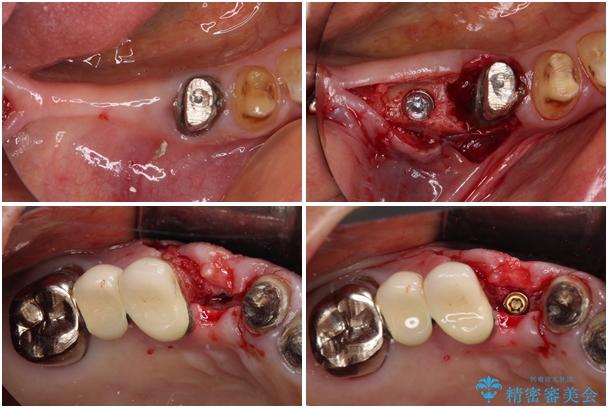

上顎犬歯や下顎大臼歯は、必要なところはインプラントを埋入することとしました。

処置を予定していた歯を仮歯に変えた時点で、下顎前歯の部分矯正を行うかどうかを尋ねたところ、折角なので行いたいと言うことでしたので、矯正治療を行うこととしました。

インプラント埋入や根管治療治療など、治癒に一定の期間を要する処置の合間に矯正治療を行うことで、効率的に治療を進めて行くことができました。

治療途中

• 前歯をきれいにしたい インプラントや部分矯正を用いた総合歯科治療 治療途中画像